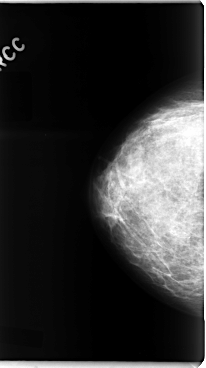

C_0091_1.RIGHT_CC

RIGHT_CC LINES 4776 PIXELS_PER_LINE 2672 BITS_PER_PIXEL 12 RESOLUTION 50 NON_OVERLAY